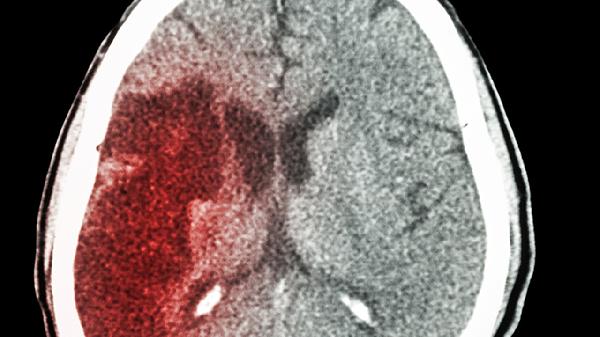

脑出血微创手术包括钻孔引流术、神经内镜血肿清除术等,具有创伤小、恢复快的优势。术后患者生命体征平稳,意识清楚,肢体活动无障碍,复查头部CT显示血肿清除满意,无再出血或脑水肿加重等情况,符合出院标准时,医生会允许患者出院。部分患者术后恢复良好,甚至可在5-7天内出院。出院后需继续遵医嘱服用降压药、神经营养药物等,定期复查头部CT,监测血压变化,避免剧烈活动或情绪激动。

若术后出现颅内感染、再出血、脑水肿加重等并发症,或患者基础疾病较多、年龄较大、恢复较慢,则可能需要延长住院时间至2周以上。少数患者因血肿位置特殊、出血量较大或合并其他脏器功能障碍,术后恢复较慢,住院时间可能超过3周。出院时间需根据个体情况综合评估,不可一概而论。